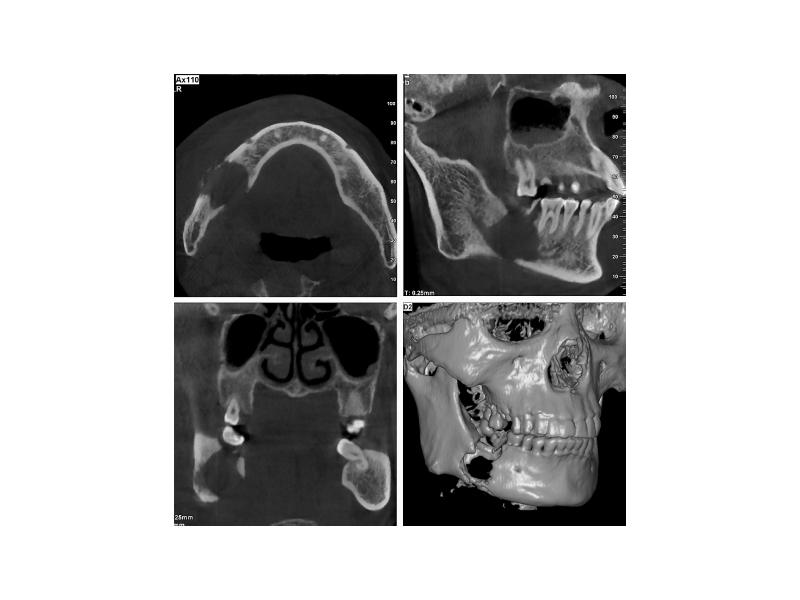

- 62. Фиброзная дисплазия Опухолеподобное заболевание моно- и полиоссальное. Поражаются кости черепа, бедренные,

- 63. Макроскопическая картина Кость деформируется вследствие ее очагового увеличения («вздутия») Рентгенологически картина

- 66. Микроскопическая картина Разрастание клеточно-волокнистой остеогенной ткани, строящей примитивные костные балочки по

- 68. Исходы Поражение в подавляющем большинстве случаев доброкачественное, но изредка наблюдается переход